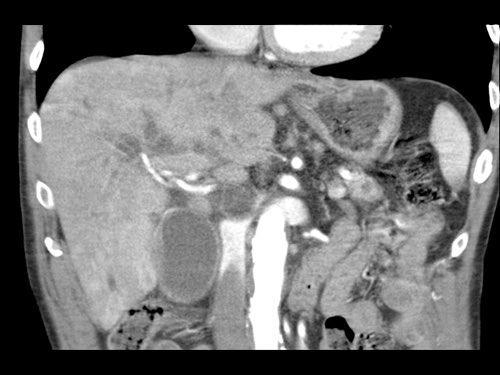

Tái tạo mặt phẳng coronal cho thấy:

- Bất thường bờ viền thành SMV được nhận thấy rõ hơn trên tái tạo coronal này (mũi tên).

- Khối u ở thân tụy (đầu mũi tên trắng).

- Huyết khối trong các nhánh bên của SMV (mũi tên xanh nhỏ).

Tái tạo mặt phẳng coronal cho thấy một khối u lớn xuất phát từ cổ tụy với kiểu phát triển xâm lấn (hình A và B).

Có hiện tượng bao quanh động mạch thân tạng 360º (mũi tên trong A).

CT axial MIP tại mức động mạch thân tạng cho thấy hẹp động mạch gan chung bị bao quanh (mũi tên), rất nghi ngờ xâm lấn.